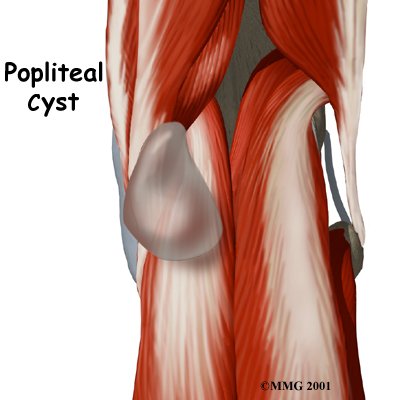

A popliteal cyst, also called a Baker's cyst, is a soft, often painless bump that develops

A popliteal cyst is a small, bag-like structure that forms when the joint lining produces too much fluid in the knee. The extra fluid builds up and pushes through the back part of the joint capsule, forming a cyst. The cyst squeezes out toward the back part of the knee in the area called the popliteal fossa, the indentation felt in the back part of the knee between the two hamstring tendons and the top part of the calf muscle.

A popliteal cyst may form after damage to the joint capsule of the knee. The weakening of the joint capsule in the damaged area can cause the small sac of fluid to form. This can lead to a bulging of the joint capsule, much like what occurs when an inner tube bulges through a weak spot in a tire. The cyst may become larger over time.